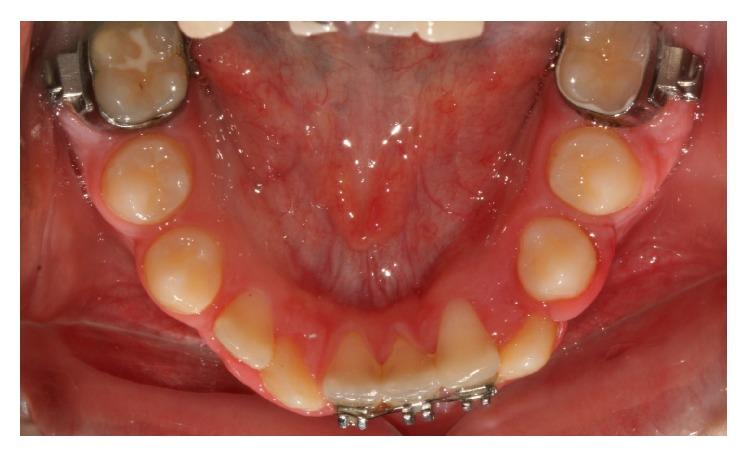

Bilateral mandibular tooth transposition is a relatively rare dental anomaly caused by distal migration of the mandibular lateral incisors and can be detected in the early mixed dentition by radiographic examination. Early diagnosis and interceptive intervention may reduce the risk of possible transposition between the mandibular canine and lateral incisor. This report illustrates the orthodontic management of bilateral mandibular canine-lateral incisor transposition. Correct positioning of the affected teeth was achieved on the left side while teeth on the right side were aligned in their transposed position. It demonstrates the outcome of good alignment of the teeth in the dental arch.

双侧下颌牙齿易位是一种相对罕见的牙齿异常,由下颌侧切牙向远中移位引起,可通过影像学检查在混合牙列早期发现。早期诊断和阻断性干预可能会降低下颌尖牙和侧切牙之间可能发生易位的风险。本报告阐述了双侧下颌尖牙-侧切牙易位的正畸治疗。左侧患牙实现了正确定位,而右侧牙齿则在其易位位置排齐。它展示了牙弓中牙齿良好排齐的效果。